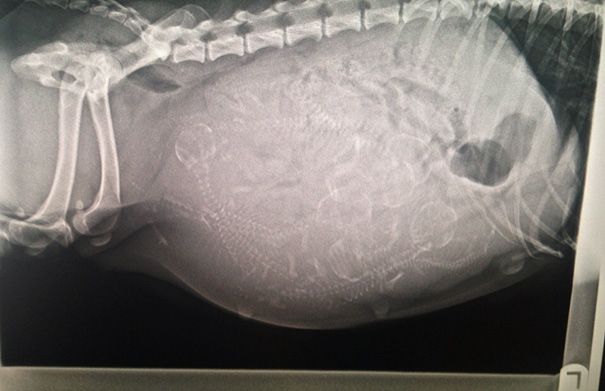

Pregnant Dog X-Ray

These are easier to see then the preg kitten. Looks like a lot of pups in there!

I hope I can't count. There's more puppies then she'll have teats to feed them.

X-rays are done before the due date to check position of babies and count the number of babies. However is it possible to miscount the babies. Babe, my mom's dog, was bred due to the rarity of her coat color. Everybody prepared for 8-10 puppies. Babe delivered 13 puppies.